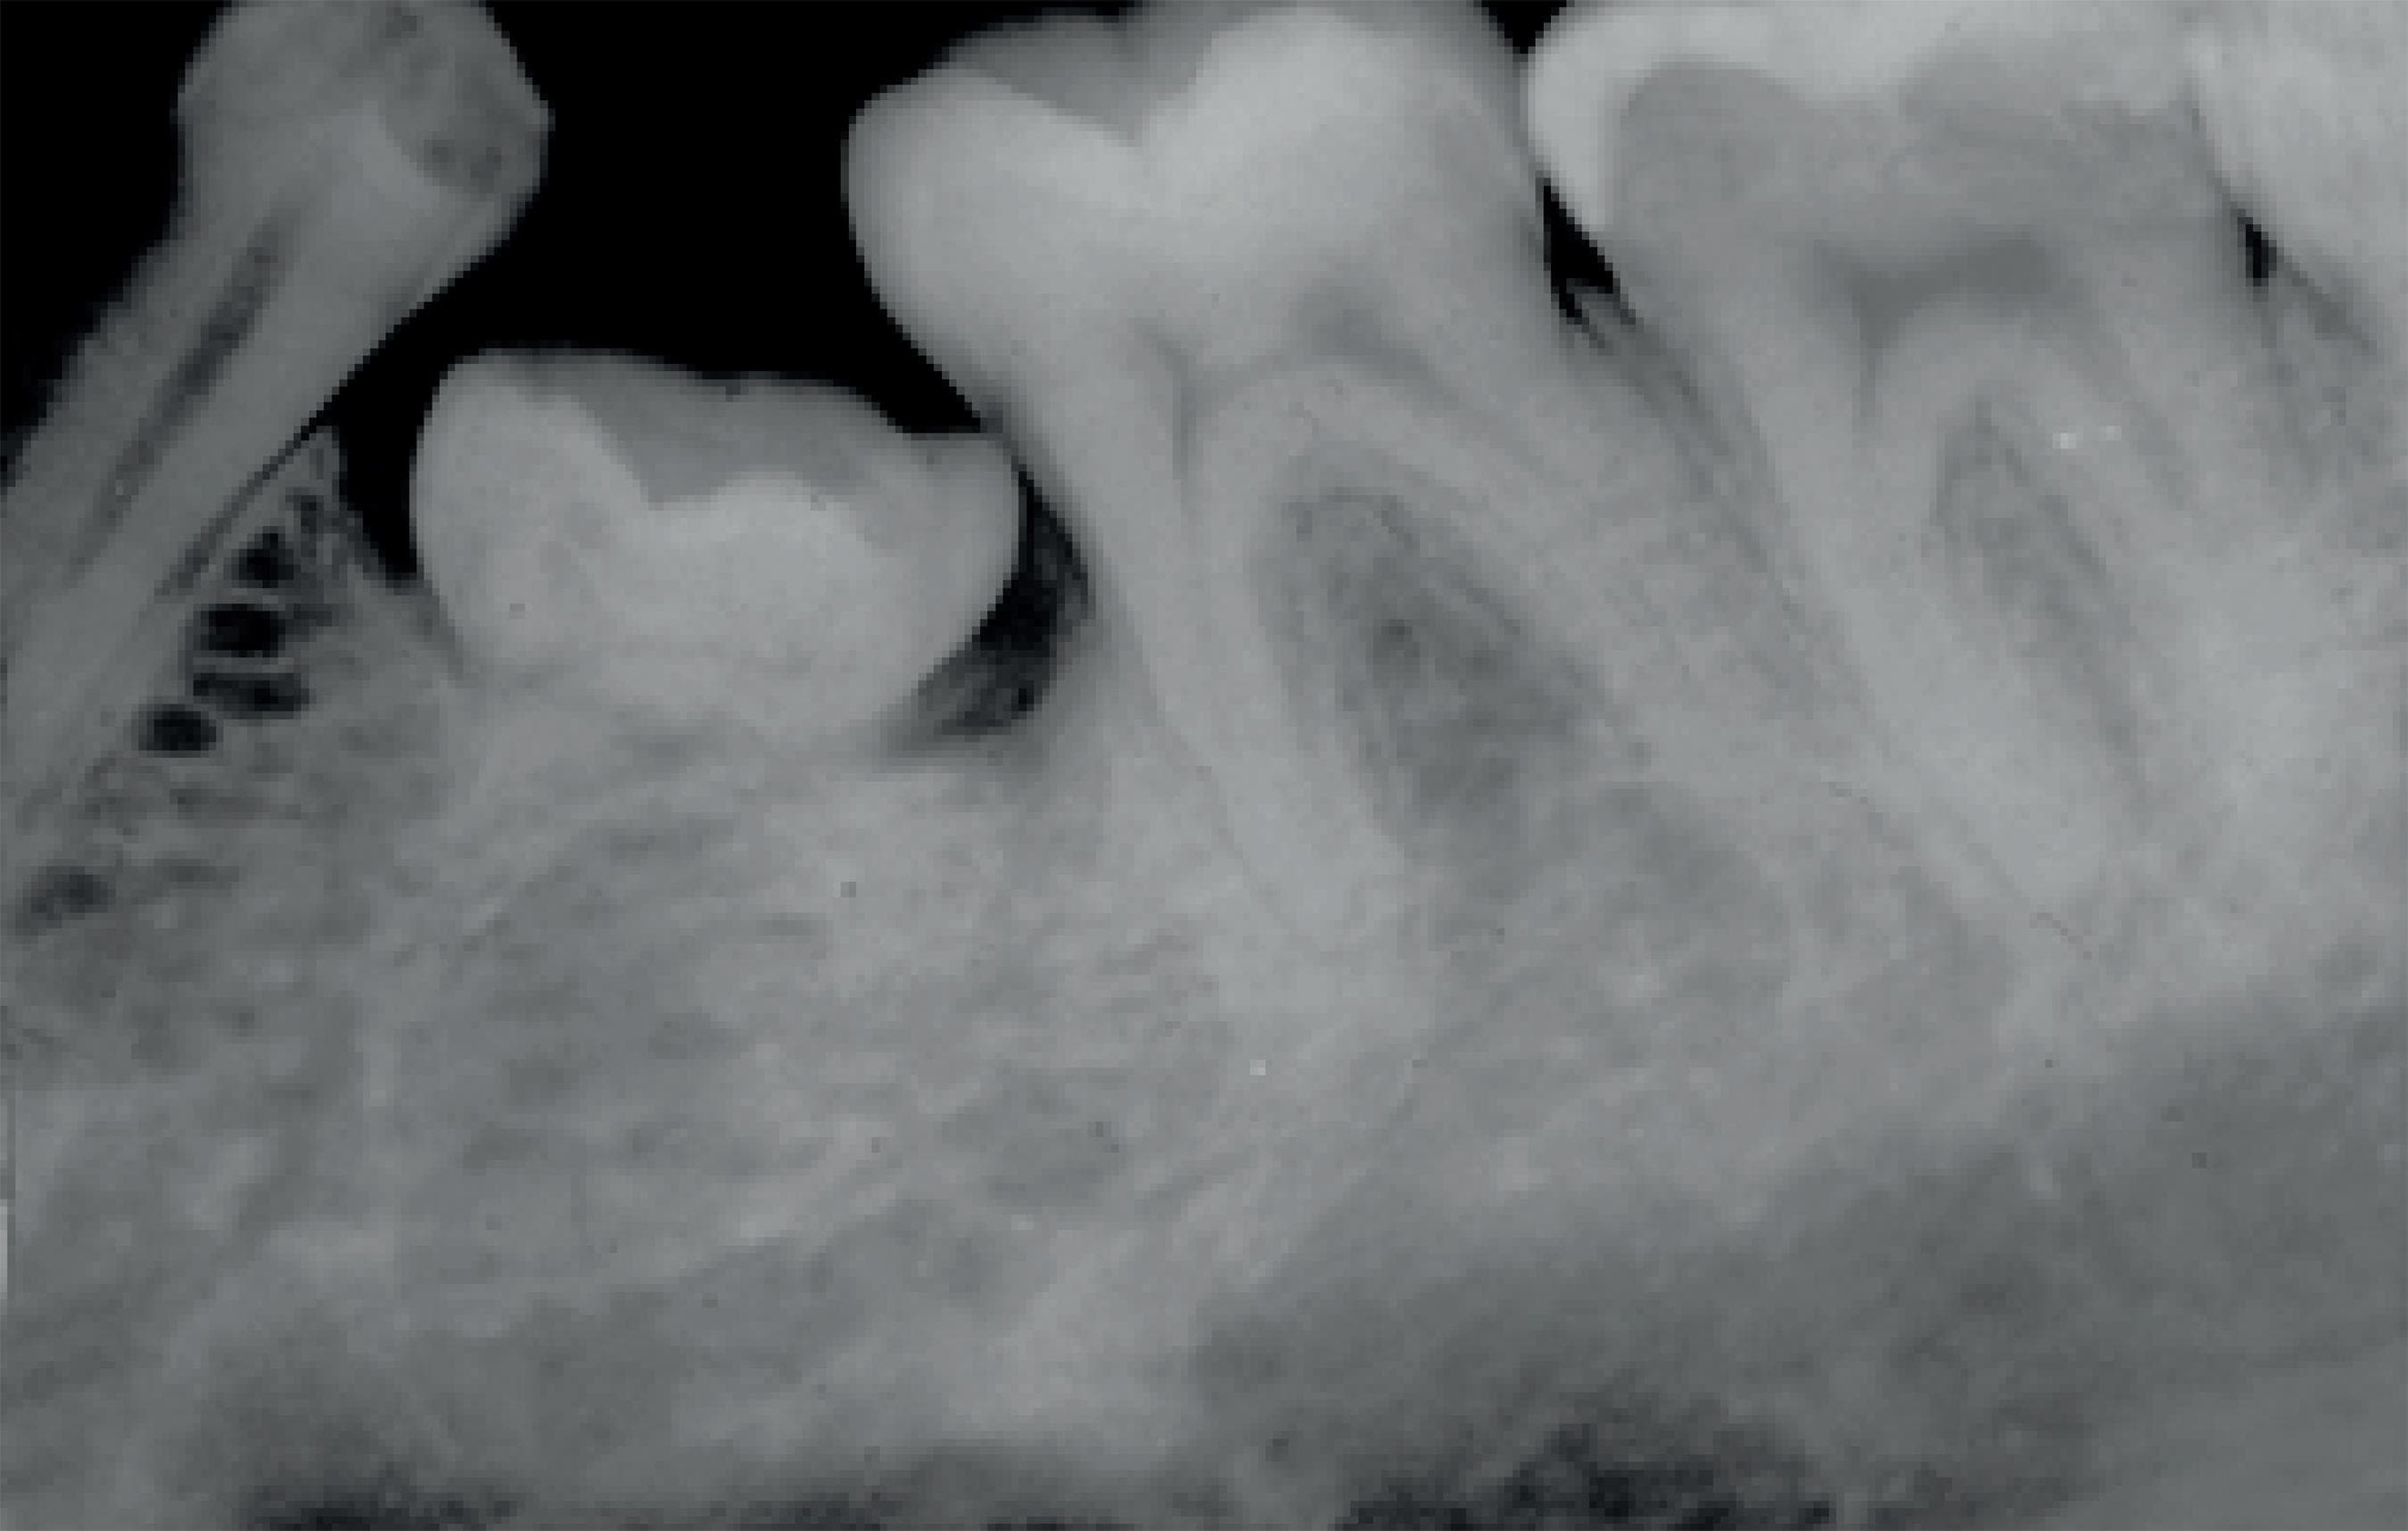

Gyökérfelszívódás

A gyökérfelszívódás a foggyökér megrövidülését jelenti. Tejfogazatban ez egy kívánatos reakció, mely a növekvő maradófog miatt jön létre. A maradófog hatására a tejfogak gyökere elkezd felszívódni, a tejfog meglazul, majd végül kiesik és helyét átveszi a megfelelő maradófog. Sajnos ez a folyamat maradófogazatban is megfigyelhető. Oka lehet fogakat ért baleset, trauma, súlyos fertőzés, de fogszabályozó kezeléseknél is előfordul. Ennek megfelelően a gyökérfelszívódások csoportosítása: belső - gyulladásos eredetű (pl.: fogbélgyulladás miatt), felületi (fogszabályozás során) és helyettesítő (balesetet szenvedett fogaknál).

Fogszabályozás során felületi, gyulladásmentes gyökérfelszívódás alakulhat ki. Fontos tisztában lenni azzal a ténnyel, hogy gyökérfelszívódás minden fogszabályozó kezelés során fellép, csupán oly kis mértékű, hogy nem lehet diagnosztizálni! A fogmozgatás miatt a foggyökerek csúcsa lekerekedik, majd a kezelés végén spontán helyreáll.

Ritkán, súlyos esetben a foggyökér jelentős megrövidülése jön létre. Ennek mértéke megjósolhatatlan, akár a fog meglazulásához, elvesztéséhez is vezethet. Legtöbbször 1-1 fogat érint, a generalizált, teljes fogazatot érintő gyökérfelszívódás extrém ritka.

Kialakulásának pontos oka még nem ismert, több faktor együttes jelenléte szükséges, és valószínűleg genetikai háttere is van. Hajlamosító tényező lehet a korábban balesetet szenvedett fog, vagy ha a kezelés során túl nagy erőkkel mozgatjuk a fogakat. Az önligírozó fogszabályzók helyes használatával ennek lehetősége minimalizálható.